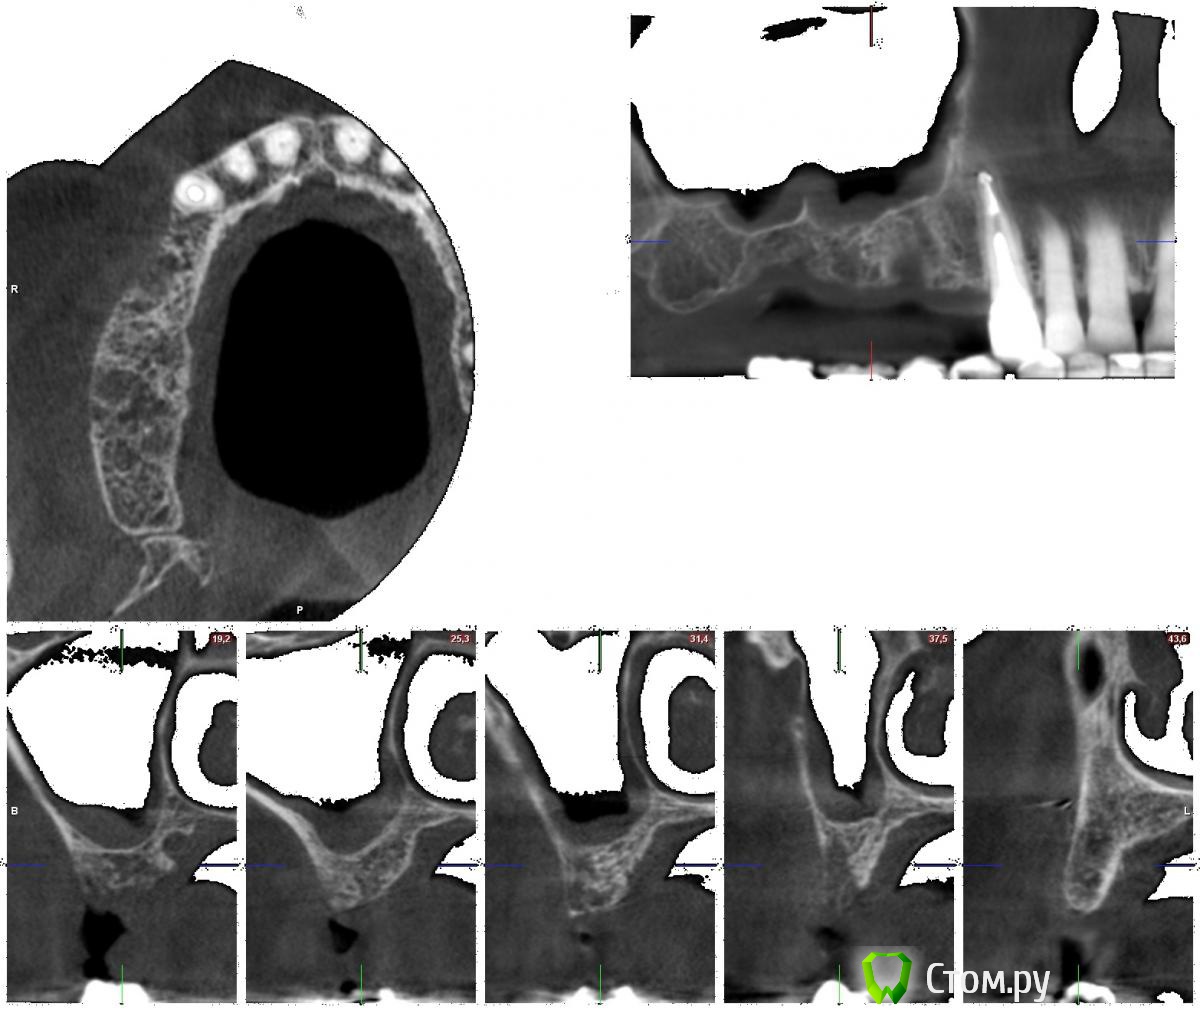

naocl Опубликовано 23 августа, 2014 Поделиться Опубликовано 23 августа, 2014 Здравствуйте ,уважаемые коллеги.Планировалась имплантация в области 14,15,16 .Кт сделано 5 месяцев назад через 2 мес после удаления14,15,16. На сегодняшний день прошло 8 месяцев после удаления.ПРи открытии визуально объема кости было достаточно, но при попытке установить имплант Alpha SPI не удалось достичь минимальной стабильности даже после пилотной фрезы.Ранее пациенту установлено 5 имплантов на вч и нч. Стабильность была.Что делать с этим сегментом?Спасибо за внимание. Ссылка на комментарий

naocl Опубликовано 24 августа, 2014 Автор Поделиться Опубликовано 24 августа, 2014 стабильности вообще никакой небыло. Имплантовод не мог вытащить. В проекции 15 вестибулярка рассыпалась в труху при установке. Ссылка на комментарий